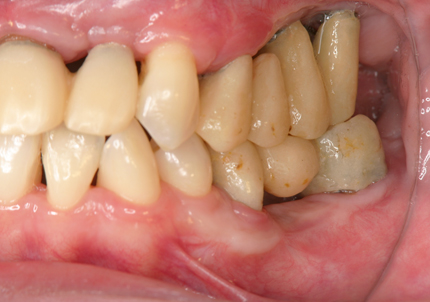

1.初診時口腔内(2007年6月30日)

↑ 2007年6月30日(初診)